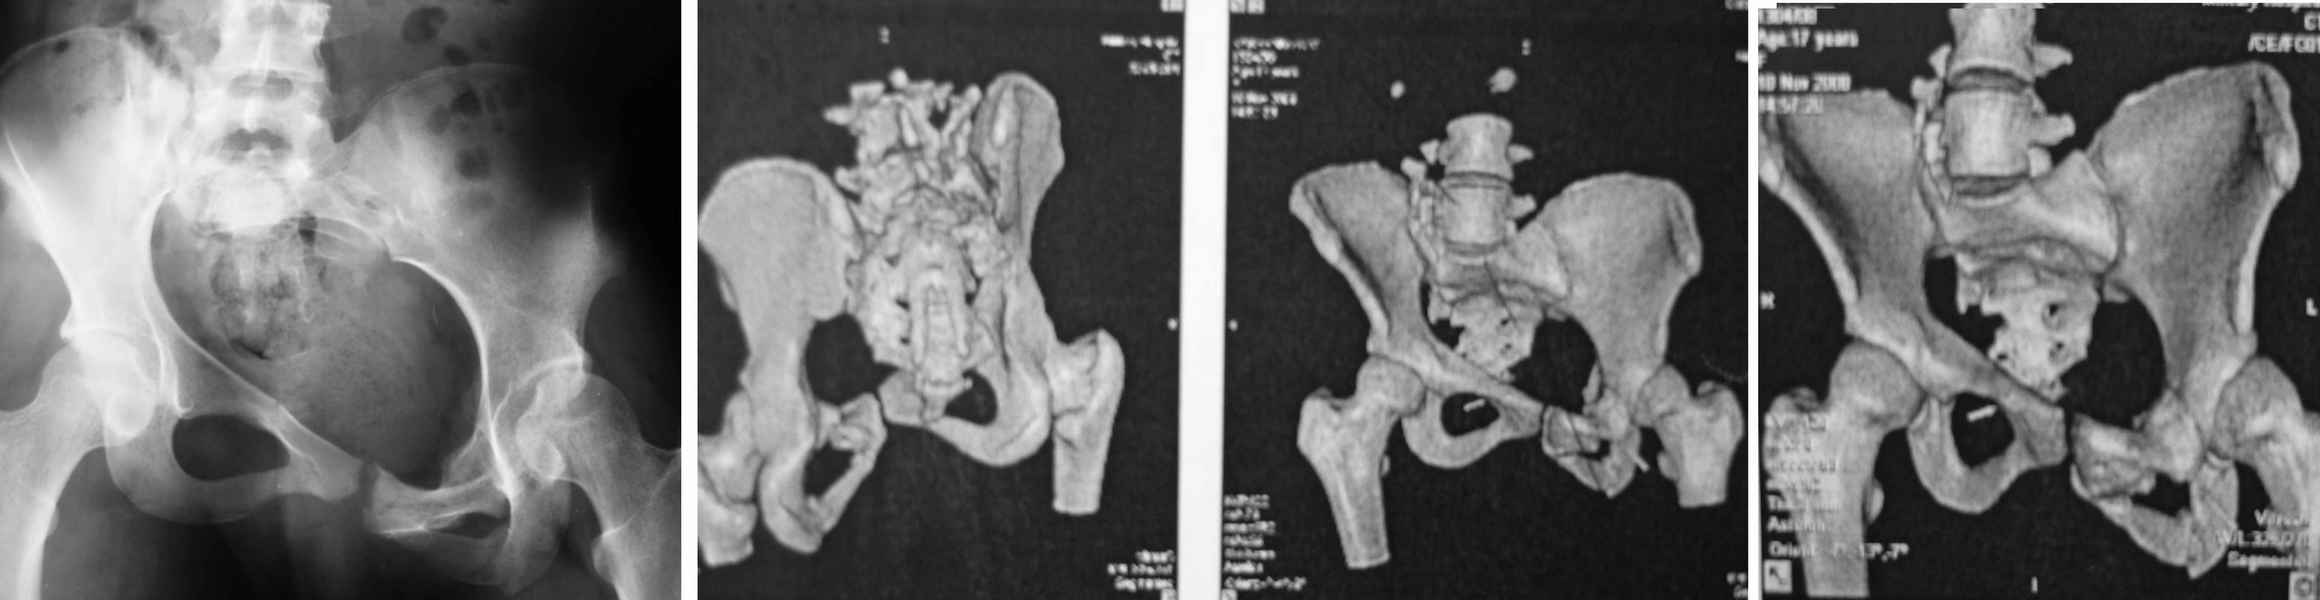

Описанная скудная клиническая картина и всего три снимка не дают возможности оценить реальную картину. 3В - красивый снимок, но не дает нужную информацию, особенно о крестцово-подвздошном сочленении.

Коллеги правы, необходимо дообследование ренгенологически и также клинически.

На представленных снимках образцы тазовых модели.